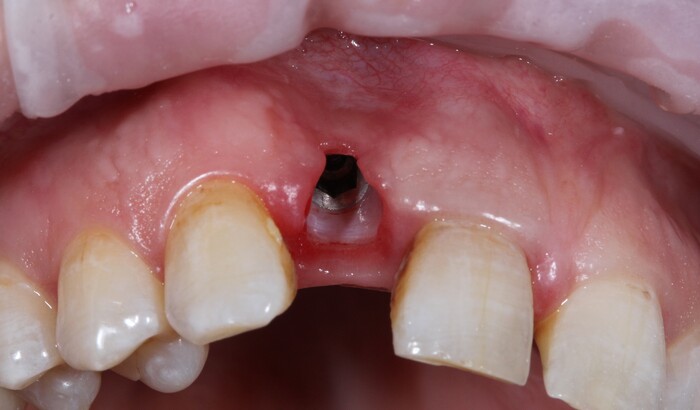

Выкрутили абатмент:

Установлена заглушка, которая закрывает шахту имплантата.